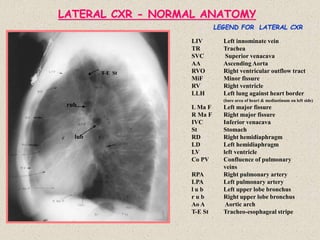

– Peripheral lymphadenopathy, hepatosplenomegaly

– Cutaneous manifestation: lupus pernio, psoriasis like plaques, erythema nodosum

– Bone & Joint involvement: single/recurrent/migratory mono/polyarticular arthritis

– Occular manifestation: uveitis, possibly with conjunctival, scleral, retinal and lens

involvement

– CNS involvement: cranial nerve palsy, hypothalamic hormonal disturbances

– Miscellaneous (rare): exocrine glands, kidney, GI tract and skeletal muscle involvement

There is a radiographic staging of Sarcoidosis for descriptive purposes

Stage 0: No demonstrable abnormality

Stage 1: Hilar and mediastinal lymph node enlargement with no

pulmonary abnormality

Stage 2: Hilar and mediastinal lymph node enlargement plus diffuse

pulmonary disease

Stage 3: Diffuse pulmonary disease only with no node enlargement

Stage 4: Pulmonary Fibrosis/End stage lung

 Lymphadenopathy: often symmetrical and bilateral, tracheobronchial, paratracheal and

bronchopulmonary. Lobulated and calcified (rare)

 Pulmonary Disease: 3 Distinctive patterns

(1) Reticulonodular pattern: ranging from purely nodular to purely reticular pattern with

fine/coarse reticular network and miliary pattern (rare)

(2) Acinar pattern: discrete or coalescent ill-defined 6-7mm opacities, may be associated

with air bronchogram and frequently a reticulonodular pattern giving “acinar shadow”.

Upper zone fibrosis and bullae may be seen. Pulmonary fibrosis may be seen as disease

progresses.

(3) Large Nodules: Sharply marginated nodular opacities with average diameter > 1cm

 Other roentgenographic abnormalities: